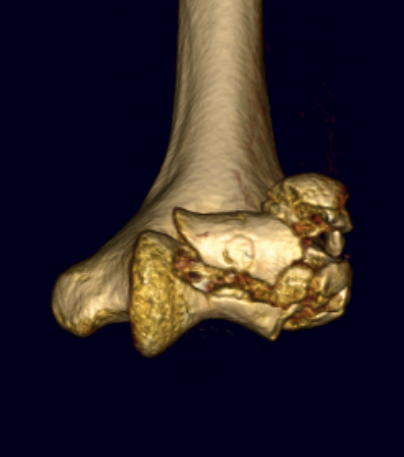

capcapcap

Capitellum fracture with radial head fracture

capcap

Capitellum fracture with radial head dislocation due to LCL injury